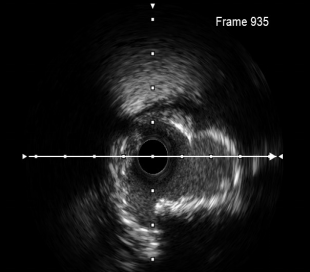

旋磨后示全程钙化斑块旋断裂